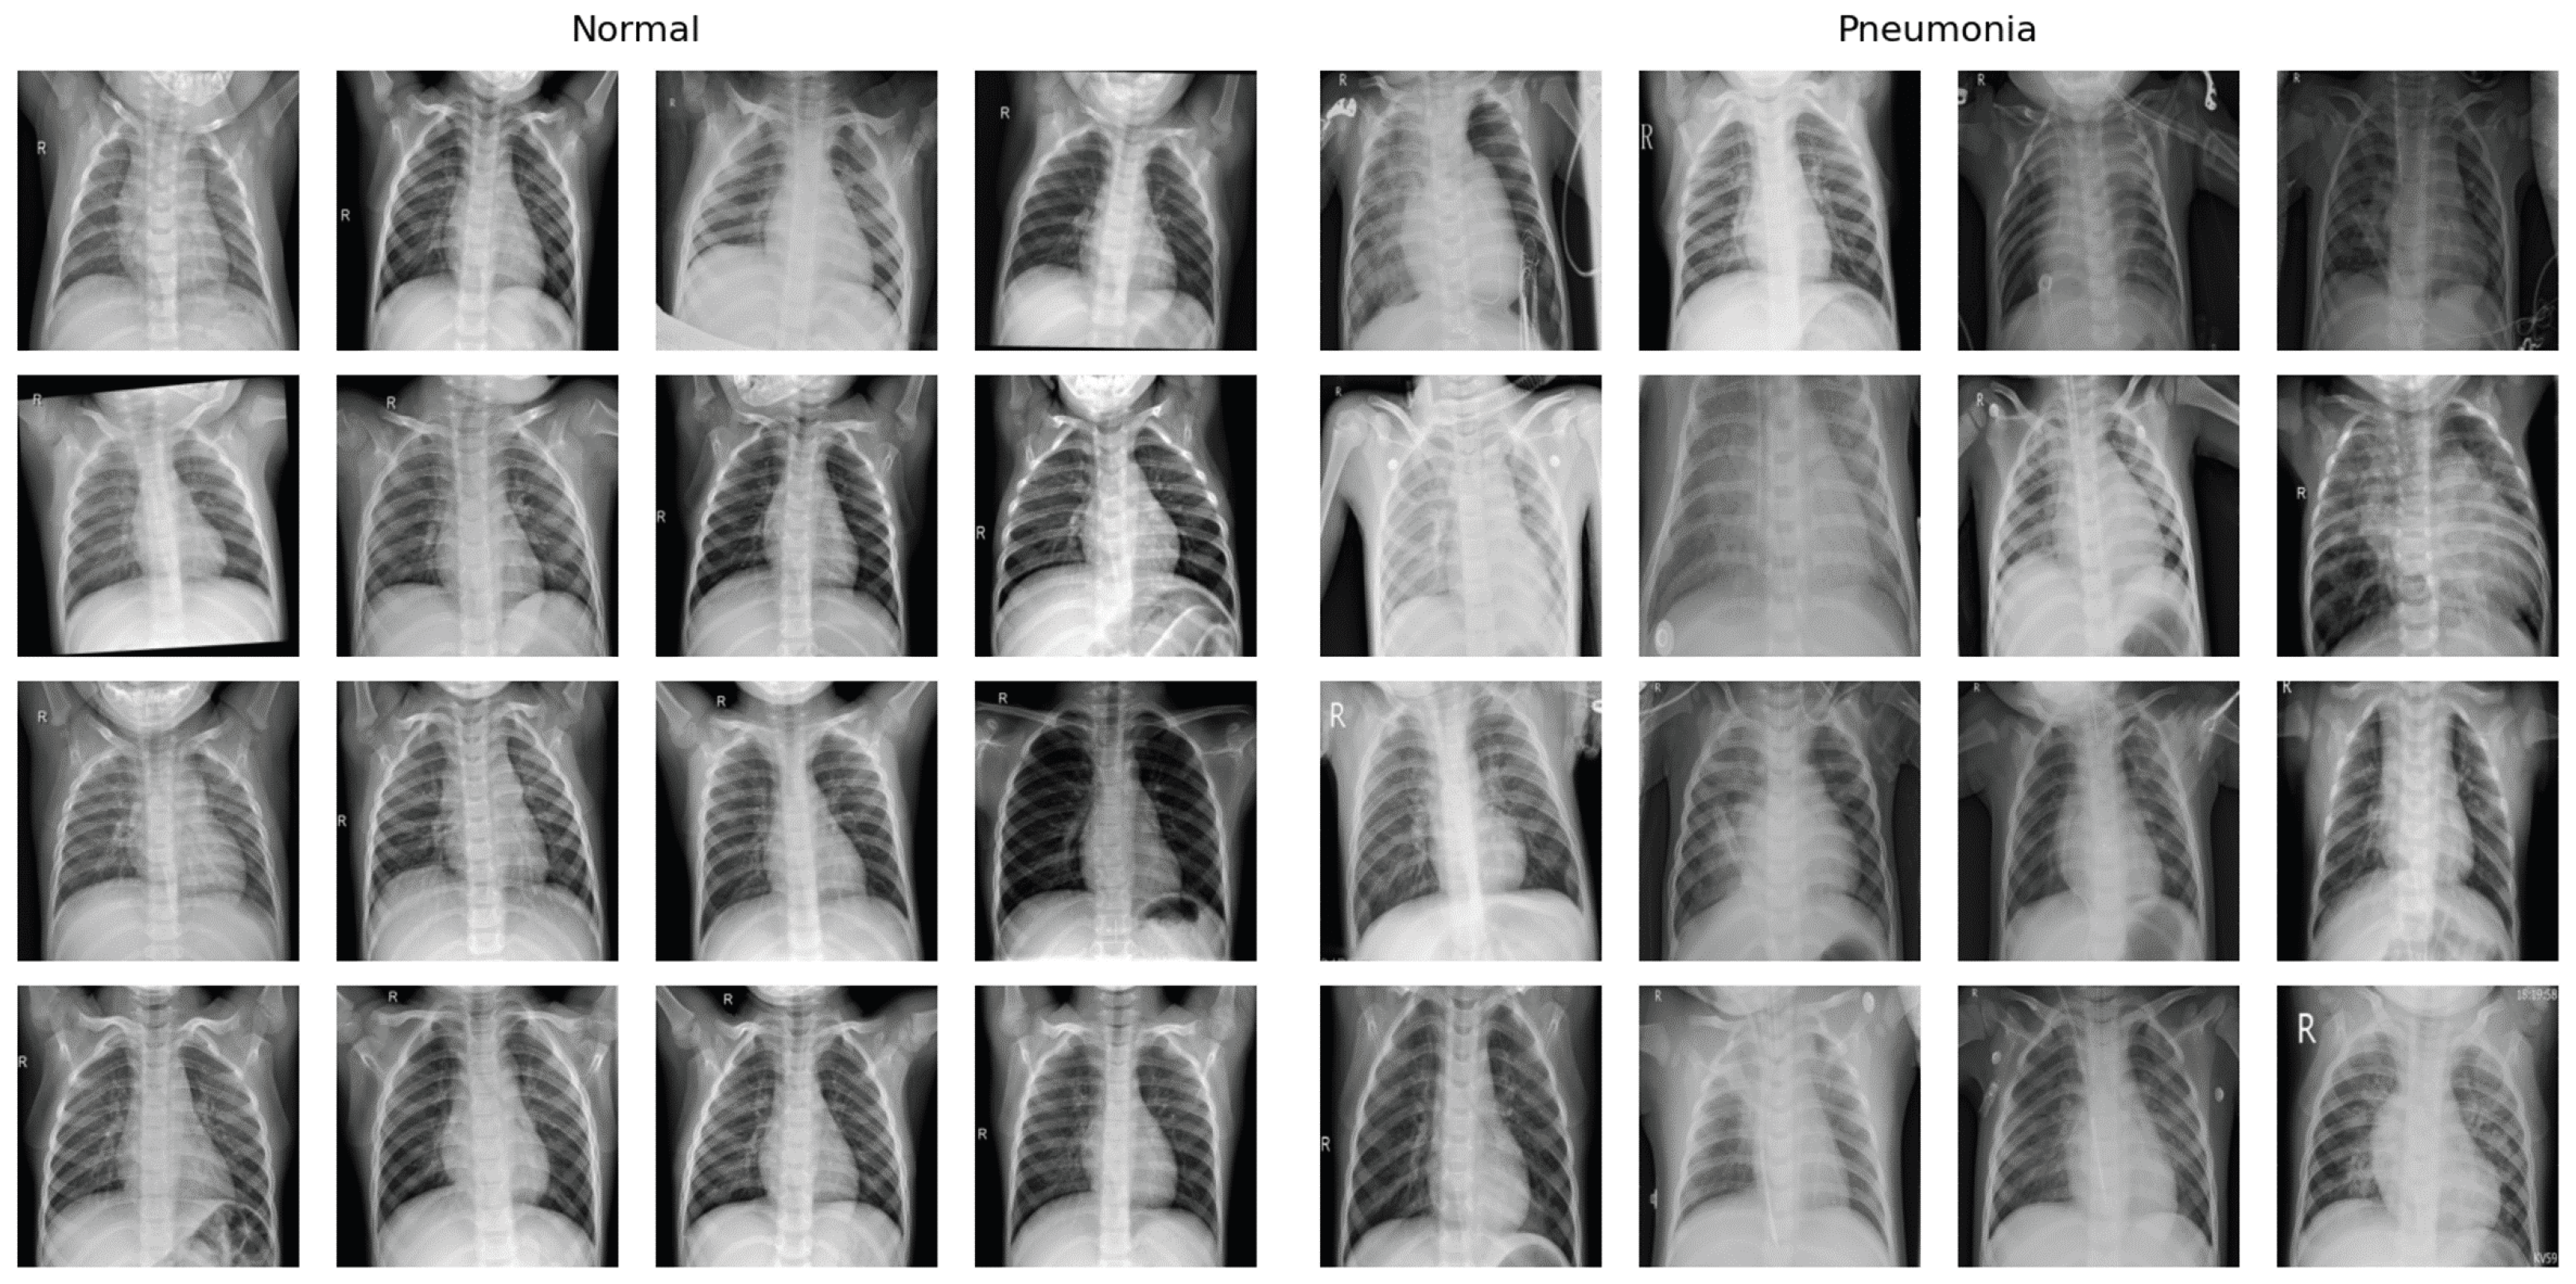

5.8. Dataset

The Pneumonia X-ray dataset, which contains a total of 5863 X-ray images categorized into Pneumonia and Normal, was used for this study. The dataset is divided into training and testing sets, with 1341 normal and 3875 pneumonia images in the training set and 234 normal and 390 pneumonia images in the testing set. Large disparities in the distribution of classes represent a common challenge in medical datasets, which we addressed during the training phase by using class weights in the loss function. The sample distribution and example images of each class are displayed in Table 1 and Figure 2.

Figure 2. Example X-ray images of each class within the Pneumonia X-ray dataset. The images on the left showcase normal X-ray images and the images on the right showcase pneumonia images.